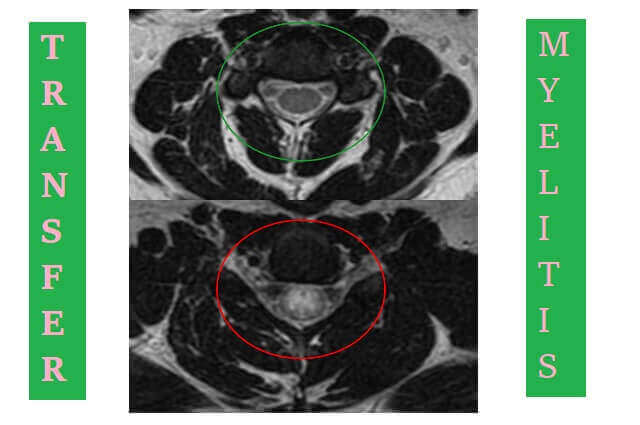

Magnetic Resonance Imaging (MRI)

Magnetic Resonance Imaging (MRI) is an examination with radio waves that produces a three-dimensional image to see the state of the brain, spinal cord. An MRI of the spine will almost always confirm the presence of lesions or inflammation of the spinal cord, while an MRI of the brain can provide clues to underlying causes, such as multiple sclerosis, given that transverse myelitis can attack both the spinal cord and brain.